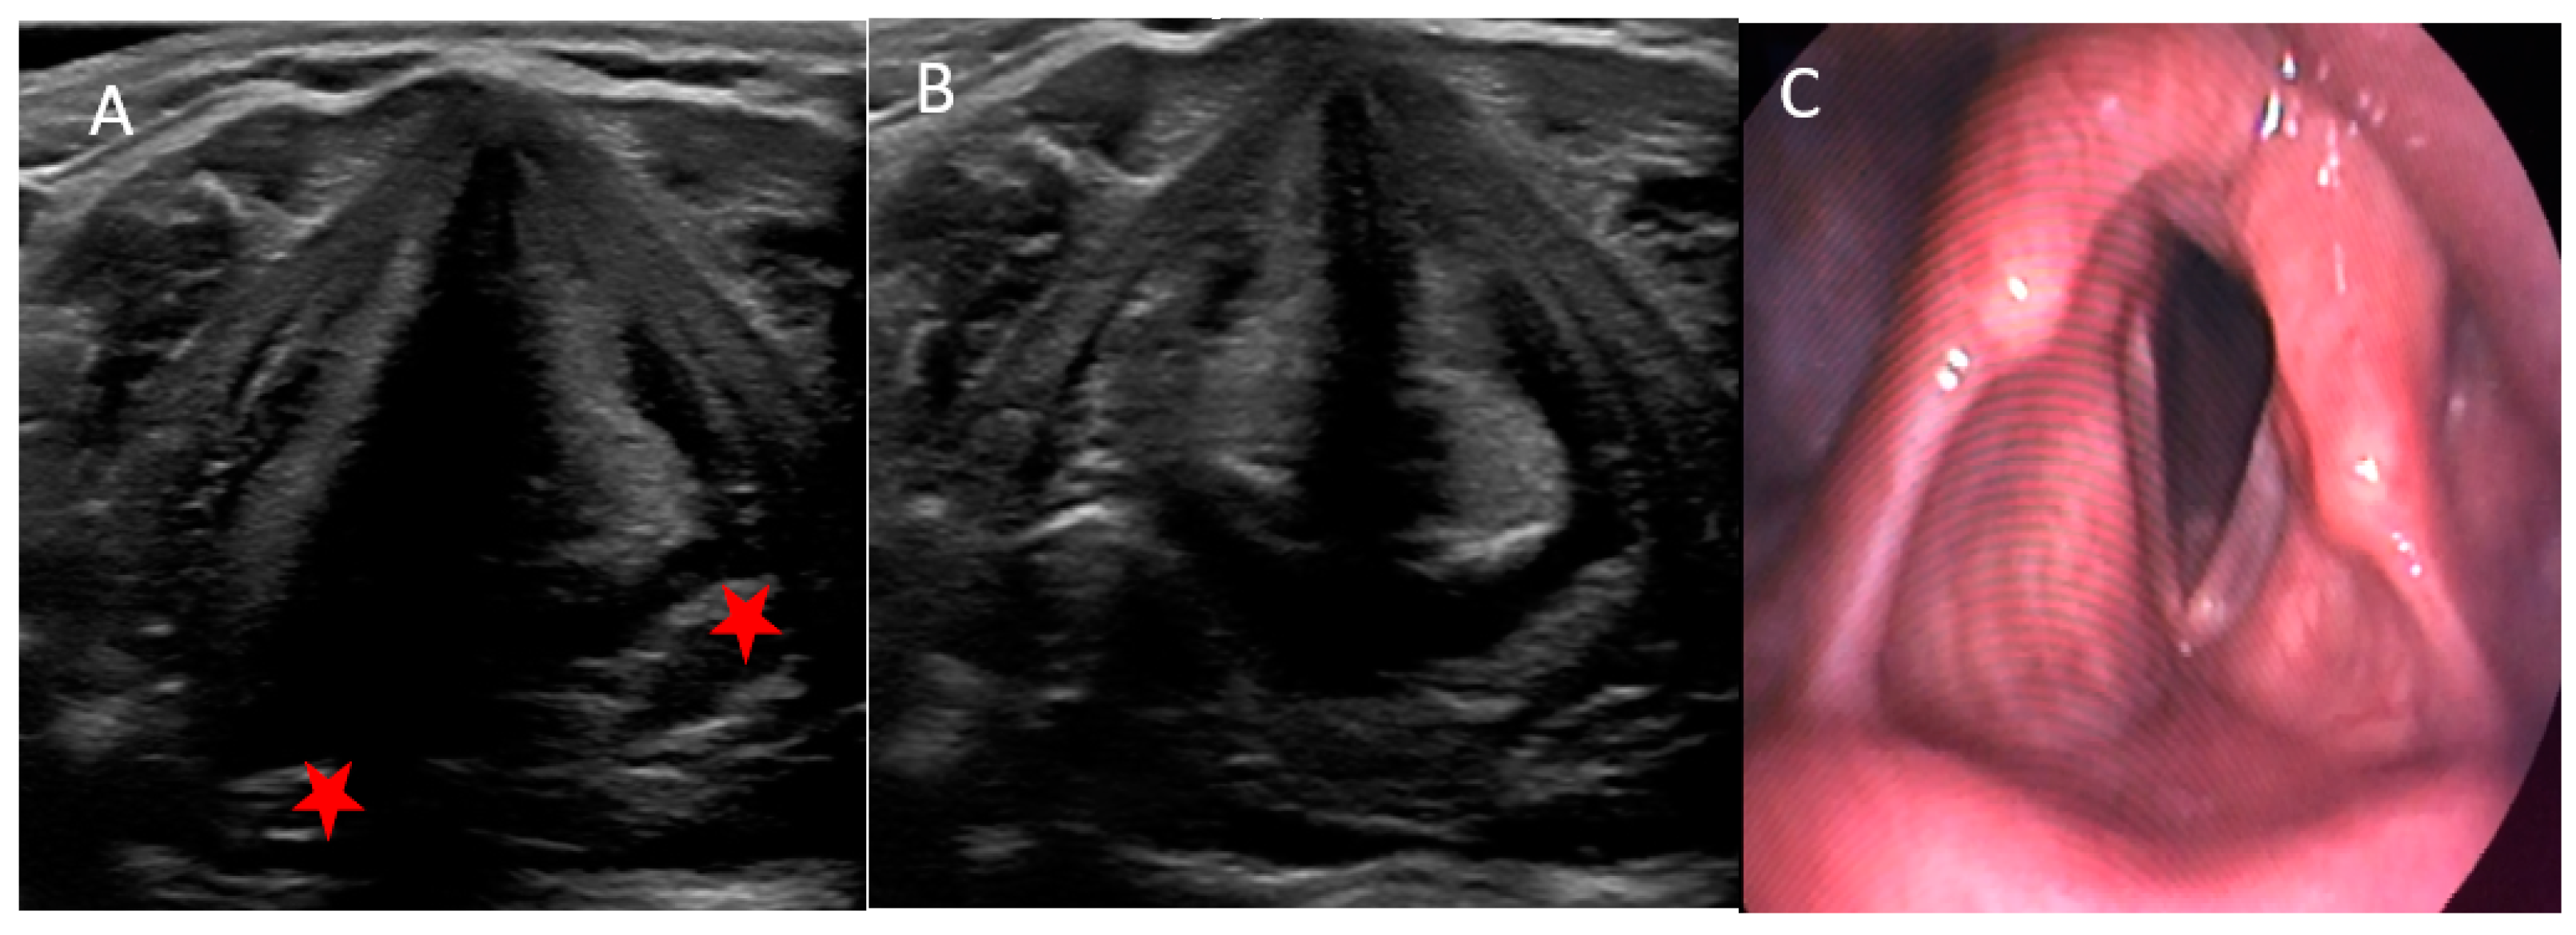

3.2. Ultrasonographic and Laryngoscopic Findings